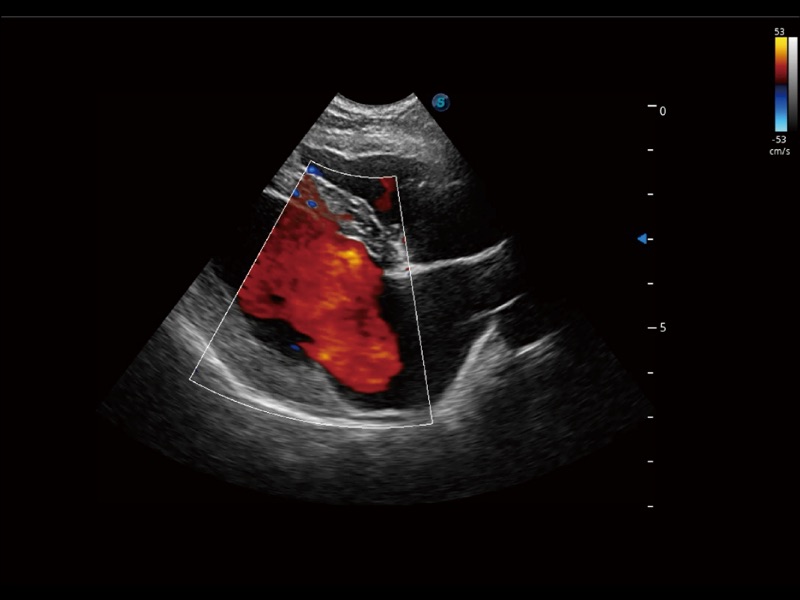

通過(guò)創(chuàng)新的 Matrix E自適應(yīng)濾波器和超長(zhǎng)時(shí)間域算法,極大提升超低速微細(xì)血流的檢出能力,同時(shí)更精準(zhǔn)地濾除軟組織和噪聲信號(hào),為獸用醫(yī)生提供以往無(wú)法通過(guò)常規(guī)血流獲得的疾病診斷信息。

通過(guò)色彩血流和實(shí)時(shí)寬景相結(jié)合,可觀(guān)察到完整的靜脈或動(dòng)脈的血流,方便醫(yī)生檢查。實(shí)時(shí)掃查過(guò)程中,如有任何操作失誤也可以很容易地進(jìn)行回掃擦除,而不會(huì)中斷掃查。

采用紅、橙、黃、綠、青、藍(lán)、紫這七種肉眼最為敏感的色彩,直觀(guān)地顯示組織內(nèi)血流灌注的時(shí)間先后信息,更精準(zhǔn)捕捉血流灌注走行細(xì)節(jié)。